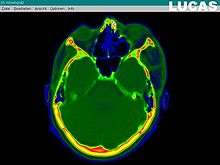

Image gathering ("segmentation") on the LUCAS workstation

Creating a virtual image of the patient

The most important component for CAS is the development of an accurate model of the patient. This can be conducted through a number of medical imaging technologies including CT, MRI, x-rays, ultrasound plus many more. For the generation of this model, the anatomical region to be operated has to be scanned and uploaded into the computer system. It is possible to employ a number of scanning methods, with the datasets combined through data fusion techniques. The final objective is the creation of a 3D dataset that reproduces the exact geometrical situation of the normal and pathological tissues and structures of that region. Of the available scanning methods, the CT is preferred,[1] because MRI data sets are known to have volumetric deformations that may lead to inaccuracies. An example data set can include the collection of data compiled with 180 CT slices, that are 1 mm apart, each having 512 by 512 pixels. The contrasts of the 3D dataset (with its tens of millions of pixels) provide the detail of soft vs hard tissue structures, and thus allow a computer to differentiate, and visually separate for a human, the different tissues and structures. The image data taken from a patient will often include intentional landmark features, in order to be able to later realign the virtual dataset against the actual patient during surgery. See patient registration.

Image analysis involves the manipulation of the patients 3D model to extract relevant information from the data. Using the differing contrast levels of the different tissues within the imagery, as examples, a model can be changed to show just hard structures such as bone, or view the flow of arteries and veins through the brain.